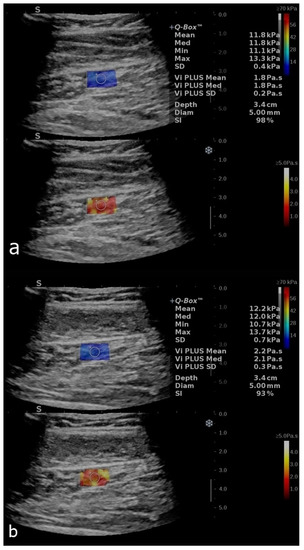

Shear-Wave Elastography and Viscosity PLUS for the Assessment of Peripheric Muscles in Healthy Subjects: A Pre- and Post-Contraction Study

| Variables | Deltoid (Precontraction) Mean ± SD 95% CI of Mean | Deltoid (Postcontraction) Mean ± SD 95% CI of Mean | Soleus (Precontraction) Mean ± SD 95% CI of Mean | Soleus (Postcontraction) Mean ± SD Median (Range) 95% CI of Mean 25–75% Percentile |

| SWE (kPa/s) | 22.2 ± 4.4 [21.2–23.2] | 24.9 ± 5.3 [23.6–26.1] | 13.1 ± 4.7 [12–14.1] | 14.2 (4.2–31.7) [25% 11.3–75% 18.5] |

| ViPLUS (Pa.s) | 2.9 ± 0.5 [2.8–3] | 3.1 ± 0.5 [3–3.2] | 2.1 ± 0.5 [1.9–2.2] | 2.4 ± 0.6 [2.3–2.6] |